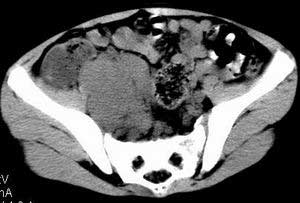

| 患者,男,9岁,因右下腹包块入院,血象不高,不规则发热,常超40度。 平扫: ![]() ![]() ![]() ![]() ![]() ![]() ![]() ![]() ![]() ![]() ![]() ![]() ![]() ![]() ![]() ![]() ![]() ![]() 增强: ![]() ![]() ![]() ![]() ![]() ![]() ![]() ![]() ![]() ![]() ![]() ![]() ![]() ![]() jiajie发言:骶椎右前区不规则软组织肿块,边缘光整,密度均匀,增强后均匀强化,右腹股沟区可见肿大淋巴结,临床有时发热,考虑淋巴瘤,儿童盆腔肿瘤应与神经母细胞瘤和横纹肌肉瘤鉴别。 longzhanghui发言:印象:盆腔右后壁不规则软组织肿块,并向前延伸.似为多个肿块融合,呈中等强化.初步考虑淋巴瘤. 听蝉观竹发言:右侧髂内、外组淋巴结肿大,从其形态和融合的情况看,同意大家意见-----考虑恶性病变,但是9岁男孩还要注意检查睾丸情况,有无隐睾? 常常类似情况是隐睾发生精原细胞瘤淋巴结转移,这个病例也要注意这一点!!! 广东凌发言:大家好,在这里我想说一下个人观点,我建议上传图片的同志能否辛苦一点就是把病史和图片都上传完整一点,比如这个病人的腹膜窗,并且这个病人的肠道的准备也是不怎么好,就从现有的质料看:病灶属于淋巴结肿大当无大的争议,有融合趋势,其内无坏死,边缘强化为主,故考虑:淋巴瘤!建议用腹膜窗看一下和肠道的关系! 阿圣发言:病灶属于淋巴结肿大当无大的争议,有融合趋势,其内无坏死,边缘强化为主,故考虑:淋巴瘤 结果是:淋巴瘤 病例来源:ct762。由宁静致远发布: http://www.radinet.com.cn/forum_view.asp?forum_id=4&view_id=2182 |